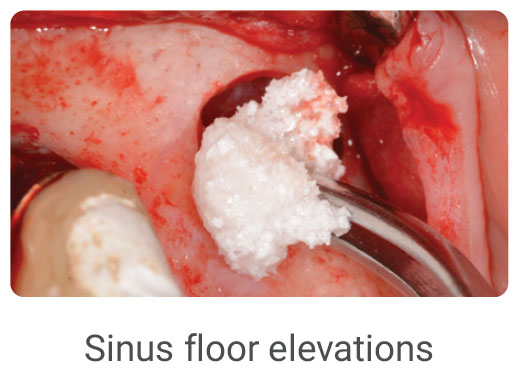

- Customizable for Various Procedures: InRoad® adapts to the unique needs of your patients.

InRoad® Dental Synthetic Bone Graft & Common Uses